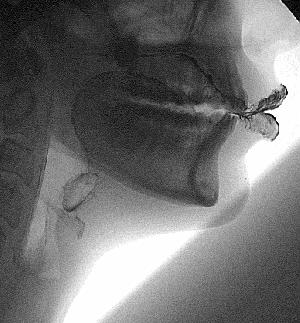

Как говорят ученые, в утробе человек проходит через все стадии эволюционного развития. Поэтому у нас когда-то был хвост, жабры и перепонки между пальцами. Возможно, вы уже это слышали, но никогда не видели.